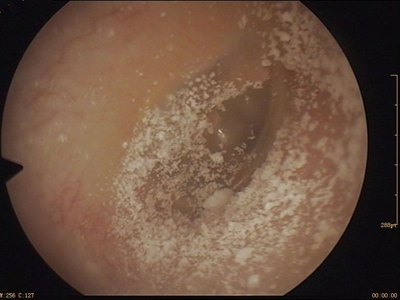

霉菌性外耳道炎外耳道结黑痂脱屑图

霉菌性外耳道炎患者外耳道周围有数量众多的黑白色鳞屑,稍微向上翘起,针尖至米粒大小,鱼鳞状排列,基地面呈紫黑色,并逐渐向外耳道深处侵袭。